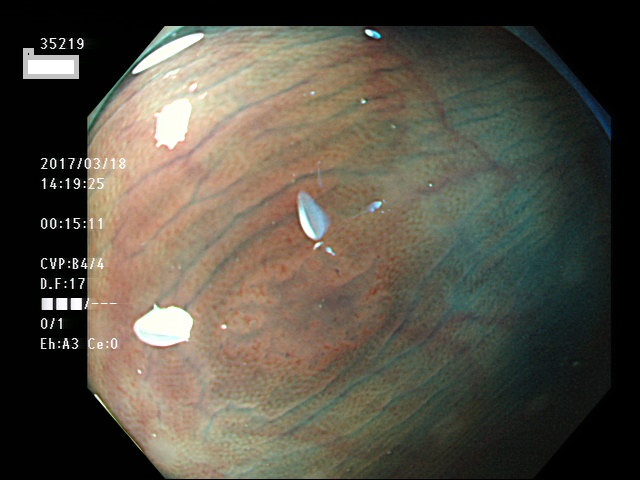

上記100名より抽出した平坦・陥凹型腺腫・SSAP(=癌化の危険が高いが見落としやすい病変)の内視鏡写真